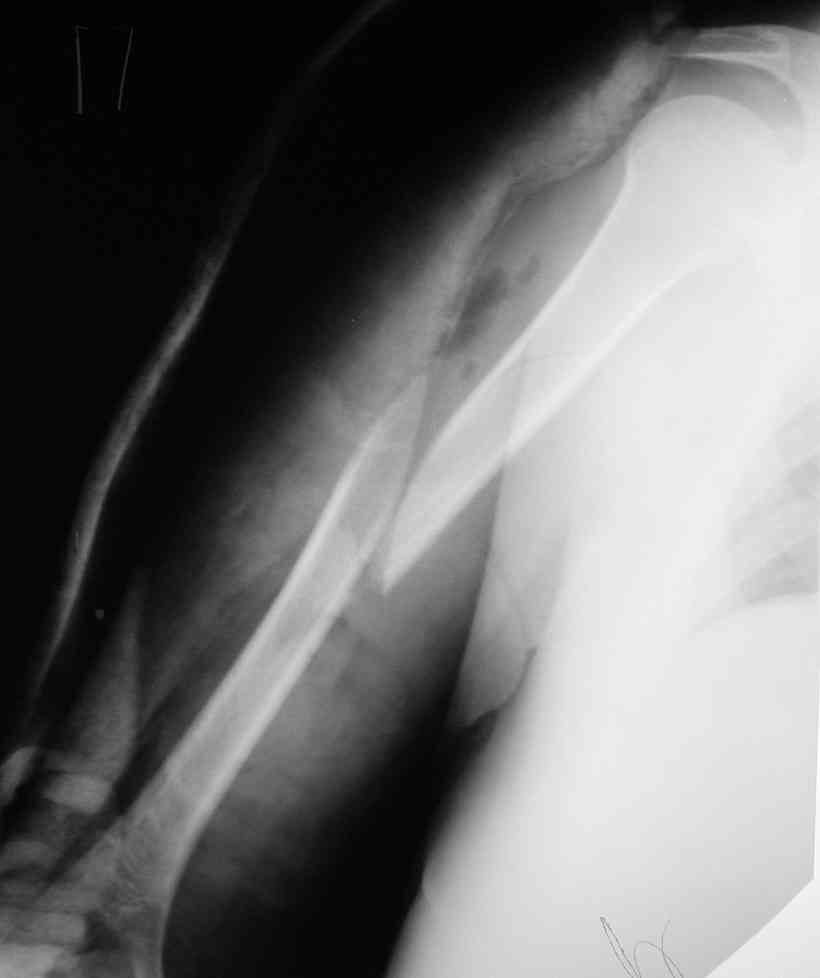

Такие надмыщелковые переломы в изолированном виде у нас в последние годы обычно фиксируются плоским титановым стержнем a la Зверев-Ключевский антеградно. Но тут еще и вышележащие проблемы.

Наверно, можно пойти на укорочение, убрав металлический цилиндр, не такой уж большой дефект. Снимки в чем-то похожего пациента прилагаю - тоже несращение диафиза после многократных операций, и надмыщелковый свежий перелом (случился после удаления обломка стержня аппарата).

Конечно, пьянство с падениями и прочими упражнениями ставит под вопрос любое дальнейшее лечение. Аппарат, что ли, еще и поверх наложить... В качестве внешнего металличкеского каркаса...